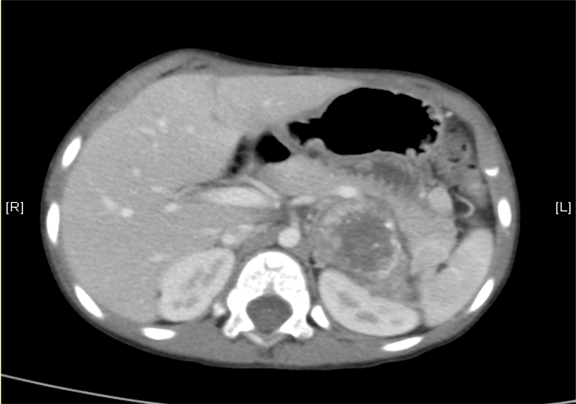

下腹部增强CT示:神经母细胞瘤。

术前CT检查:

动脉期